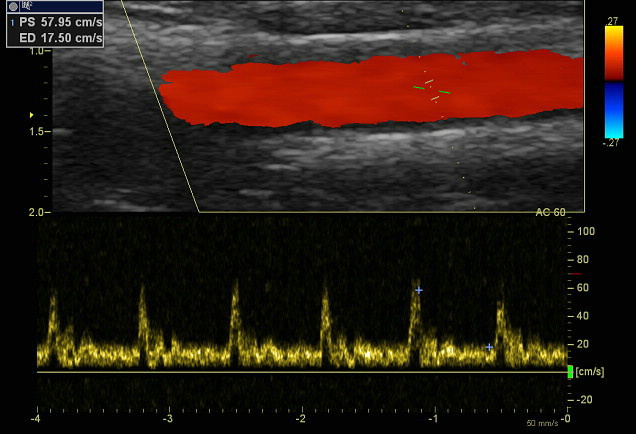

Ultrasound techniques are widely used in the diagnosis of heart diseases. Cardiac sonography enables physicians to observe problems related to heart function; providing a clear view of veins and arteries. Doppler ultrasound is extremely effective as it can show the direction and speed of blood flow, assist in the detection of obstructions like blood clots and narrowed blood vessels, and help to diagnose regurgitation. In addition, duplex ultrasound being safe and devoid of radiation and contrast dyes has become the preferred diagnostic test.

This is especially true when interference in the doppler signal results in unwanted artefacts in the colour representation. While utilising pulsed wave or continuous wave doppler with downed elements, you may experience noise or obstructions in the measured signals which can return incorrect readings of velocity and thus result in misdiagnosis of regurgitation and other complications. Below is an example of a doppler study of the carotid artery – results at risk of being inaccurately measured due to downed elements.

In a 2014 study, results confirmed that the degradation of an ultrasound probe through downed elements will negatively affect the quality of the Doppler-derived diagnostic information. The study also concluded that the results of Doppler measurements cannot be considered accurate or reliable if there are four or more contiguous dead elements in any given probe.